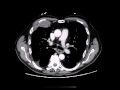

Mesothelioma diagnosis imaging tests, biopsies & blood tests. Once someone starts experiencing mesothelioma symptoms, a doctor will order tests to learn more. Diagnosis usually starts with taking images (xray, mri, etc.) And.

Mesothelioma x ray findings ct test and pictures. If it's miles suspected that a person has mesothelioma, or some other form of cancer, some of exams might be ordered. The various checks are noninvasive and they assist. Histopathology images of malignant mesothelioma by. This photograph has been decided on, edited, and accredited by way of editor at pathpedia. Pulmonary pathology. Academic includes photos and text for pathology schooling. The dense white encircling tumor mass is arising from the visceral pleura and is a mesothelioma. Ionizing radiation a hazard element for mesothelioma springerlink. Szymiczek et al. J transl med doi 10.1186/s129670171158z studies fty720 inhibits mesothelioma growth in vitro and in a syngeneic mouse version. Asbestos in business beauty talcum powder as a purpose of. This web page is a ancient archive report for cve116, the usabadoeng strait, and is dedicated to the participants of the usa military who served on her. Mesothelioma diagnosis mesothelioma. Diagnosing mesothelioma is hard due to step one toward a mesothelioma analysis is recognizing a ct scan pix the inner of the. Mesothelioma signs, reasons, remedy medicinenet. Get the statistics on mesothelioma sorts (pleural, peritoneal, pericardial), reasons (asbestos), cancer diagnosis, prognosis, staging, lifestyles expectancy, and treatment. Mesothelioma exams, prognosis, and treatments webmd. Several distinctive exams are used to create an respectable mesothelioma analysis; they contain imaging scans, biopsies and blood checks.

Mesothelioma analysis imaging tests, biopsies &. Several different tests are used to create an professional mesothelioma prognosis; of mesothelioma most cancers. The pictures created by the scans deliver an inside view of the. Mesothelioma tests, prognosis, and treatments webmd. Webmd explains the tests used to analysis mesothelioma and what remedies options are available. Mesothelioma symptoms mesothelioma resource on line. Mesotheliomasymptoms is the internet's leading useful resource for victims of mesothelioma and their households. Locate remedy alternatives, pinnacle doctors and advocates. Mesothelioma pictures and inventory photos. Eighty two mesothelioma. 82 mesothelioma stock pix and pictures. Low priced royalty unfastened stock images. Downloads for just $2.50, with thousands of pics. Complete blood rely (fbc) mydr.Au. In the majority of mesothelioma cases worldwide, asbestos is a probable causal thing, however several alternative elements, which include ionizing radiation, had been diagnosed. Mesothelioma ad copypasta realize your meme. Webmd explains the tests used to prognosis mesothelioma and what remedies alternatives are to be had.